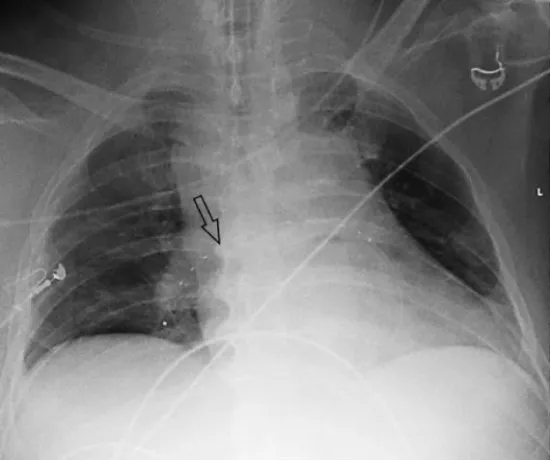

To stabilize the patient, a portable arterio-venous extracorporeal lung assist (ECLS) device (iLA activve®, Novalung GmbH, Heilbronn, Germany) was implanted via a femoral access. Furthermore, an ultrasound-assisted catheter was positioned within the right pulmonary artery and thrombolysis was performed using low-dose rtPA (0.8 mg/h) (Figure 3, Video 1). No further bleeding occurred in the 4 days of thrombolysis and the patient recovered gradually.